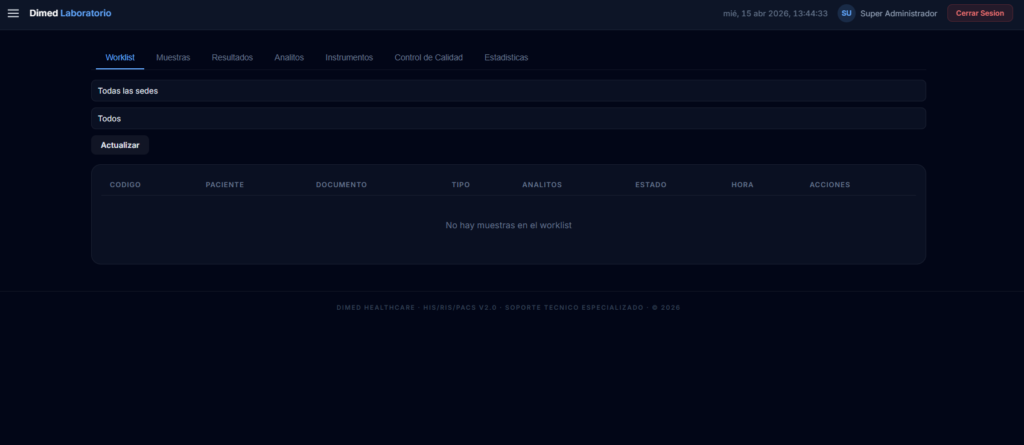

El LIS gestiona el flujo completo del laboratorio clínico, desde la recepción de muestras hasta la entrega de resultados al paciente y al médico tratante.

- Recepción de muestras: Registro, etiquetado, trazabilidad

- Órdenes de laboratorio: Perfiles de exámenes, pruebas individuales

- Resultados: Ingreso manual o automático desde analizadores

- Validación: Revisión y aprobación por profesional